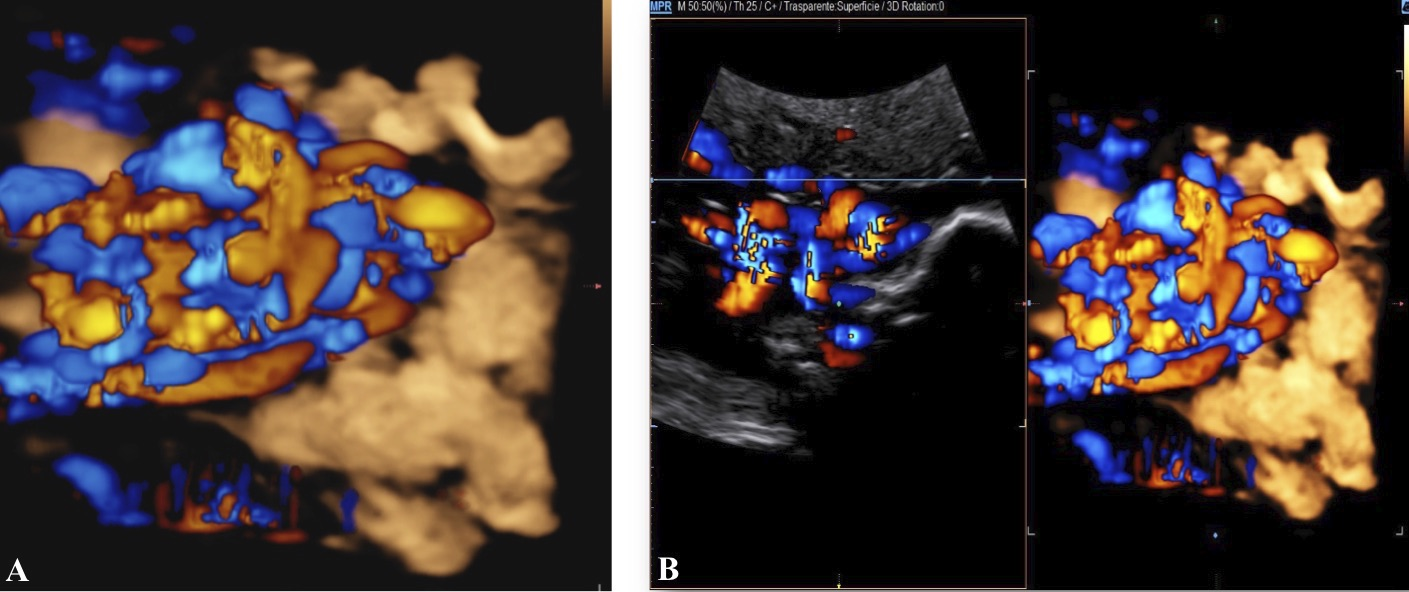

A healthy 39-year-old woman G4P3 was admitted to our high-risk pregnancy outpatient service due to a MC-DA twin pregnancy. Monochorionicity was suspected by the referring gynecologist during the dating ultrasound scan (US). The nuchal translucency US at the 12th week of gestation highlighted a “T” sign of the dividing membrane with a unique anterior placenta confirming a MC-DA twin pregnancy, as shown in Fig. 1. Soft markers for trisomy were found to be normal for both twins. The US performed during the 14th week of gestation showed the twins significantly closer to each-other standing on the same side of a free-floating thin membrane inserted on the placenta. This image raised the suspicion for a spontaneous septostomy (Fig. 2). The patient underwent amniocentesis as the combined serum screen showed an increased risk for Trisomy 21. US assisted invasive procedure did not detect the dividing membrane deposing for a PMM twin pregnancy following SS. A single sample of amniotic fluid was obtained and tested normal for fetal karyotype (46, XX). According to International Guidelines US imaging was performed every two weeks. Anomaly scan was normal and all subsequent Doppler US showed a normal twin growth and fetal wellbeing until the early third trimester [14, 15, 16]. The US performed at the 27th week of gestation showed a strict contiguity of the umbilical cords with a suspicion for cord entanglement on 3-dimensional (3D) US (Fig. 3A,B). The patient was hospitalized for close pregnancy surveillance. Fetal heart monitoring and US scan were daily performed. Steroids were administered for prevention of respiratory distress syndrome. The 29th week US scan highlighted a growth discordance ranging around 21% (symmetric growth at the 71° centile (estimated weight: 1328 gr) and at the 36° centile (estimated weight: 1043 gr) for Twin A and Twin B respectively). An episode of prolonged bradycardia was registered for Twin A. An emergency cesarean section was performed: two healthy girls were born (Twin A: weight 1360 gr, Apgar 4 and 7 at 1st and 5th minute respectively — Twin B: weight 1000 gr, Apgar 8 and 9 at 1st and 5th minute respectively). Cord entanglement was confirmed as shown in Fig. 4. The mother’s postoperative recovery was uneventful. Twins’ developmental follow-up at 12 months of age was normal.

Fig. 2.Sonogram depicting a thin free-floating membrane inserting on a unique anterior placenta with the two twins standing close to each other on the same side of the membrane.

Fig. 3.Sonograms depicting 3-dimensional imaging of cord entanglement suspected during the 27th week US.